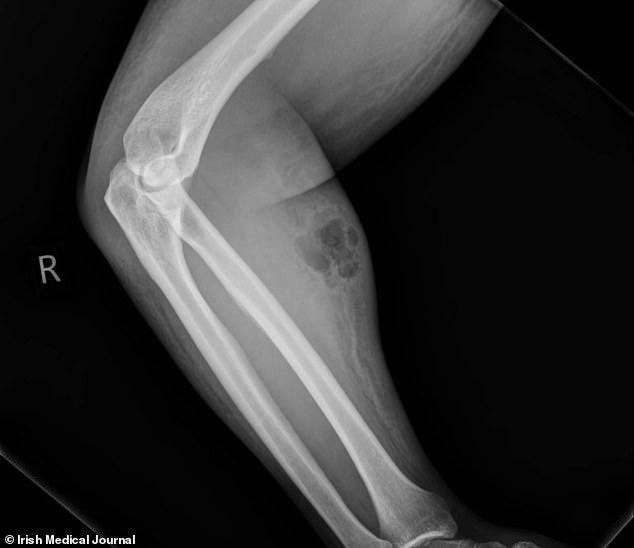

Cánh tay người đàn ông sưng đỏ vì tiêm tinh trùng trong 18 tháng

Đương nhiên, phương pháp kỳ quái này không chữa trị được chứng đau lưng mạn tính thậm chí còn khiến cánh tay phải của ông bị viêm mô tế bào - một loại nhiễm trùng dưới da hết sức nguy hiểm. Sau khi được điều trị, tình trạng của bệnh nhân đã cải thiện rõ, tuy nhiên trước khi bác sĩ kịp loại bỏ hết tinh trùng dưới cánh tay, người đàn ông đã tự ý rời khỏi.

Việm tiêm tinh trùng khiến bệnh nhân bị nhiễm trùng da